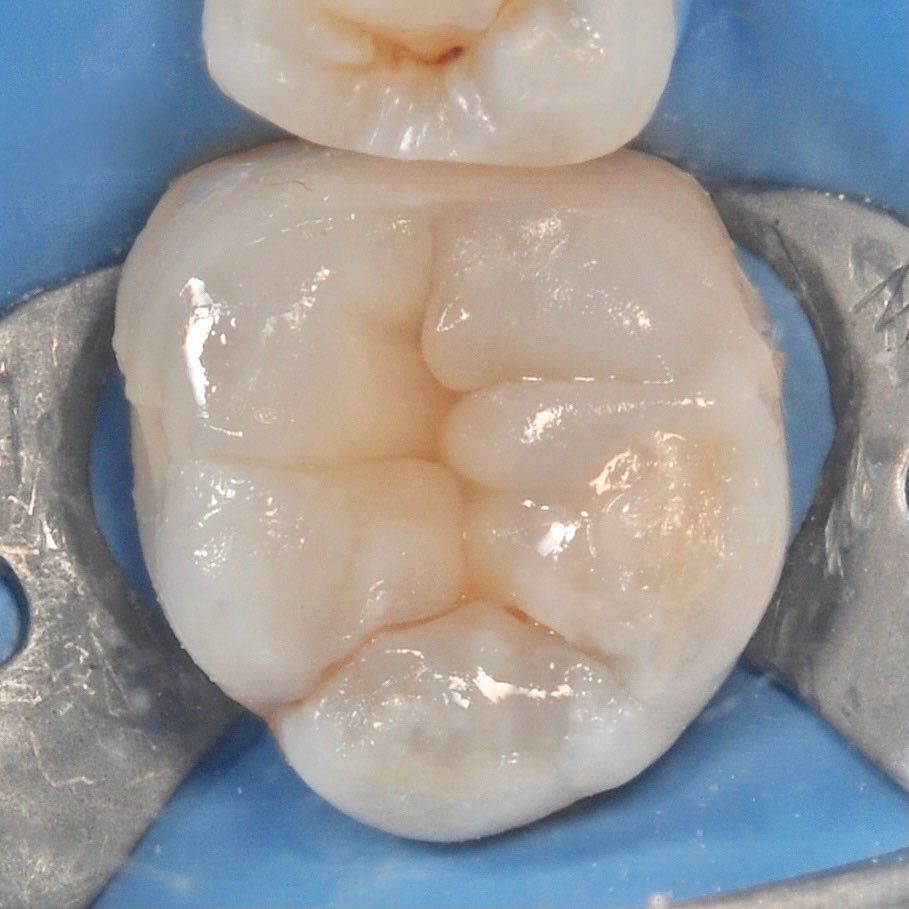

Root canal treatment

We successfully treat complex cases of canal inflammation thanks to the good equipment and experience of doctors.

careful treatment of canals

Accurate determination of the geometry of the channels and their high-quality processing